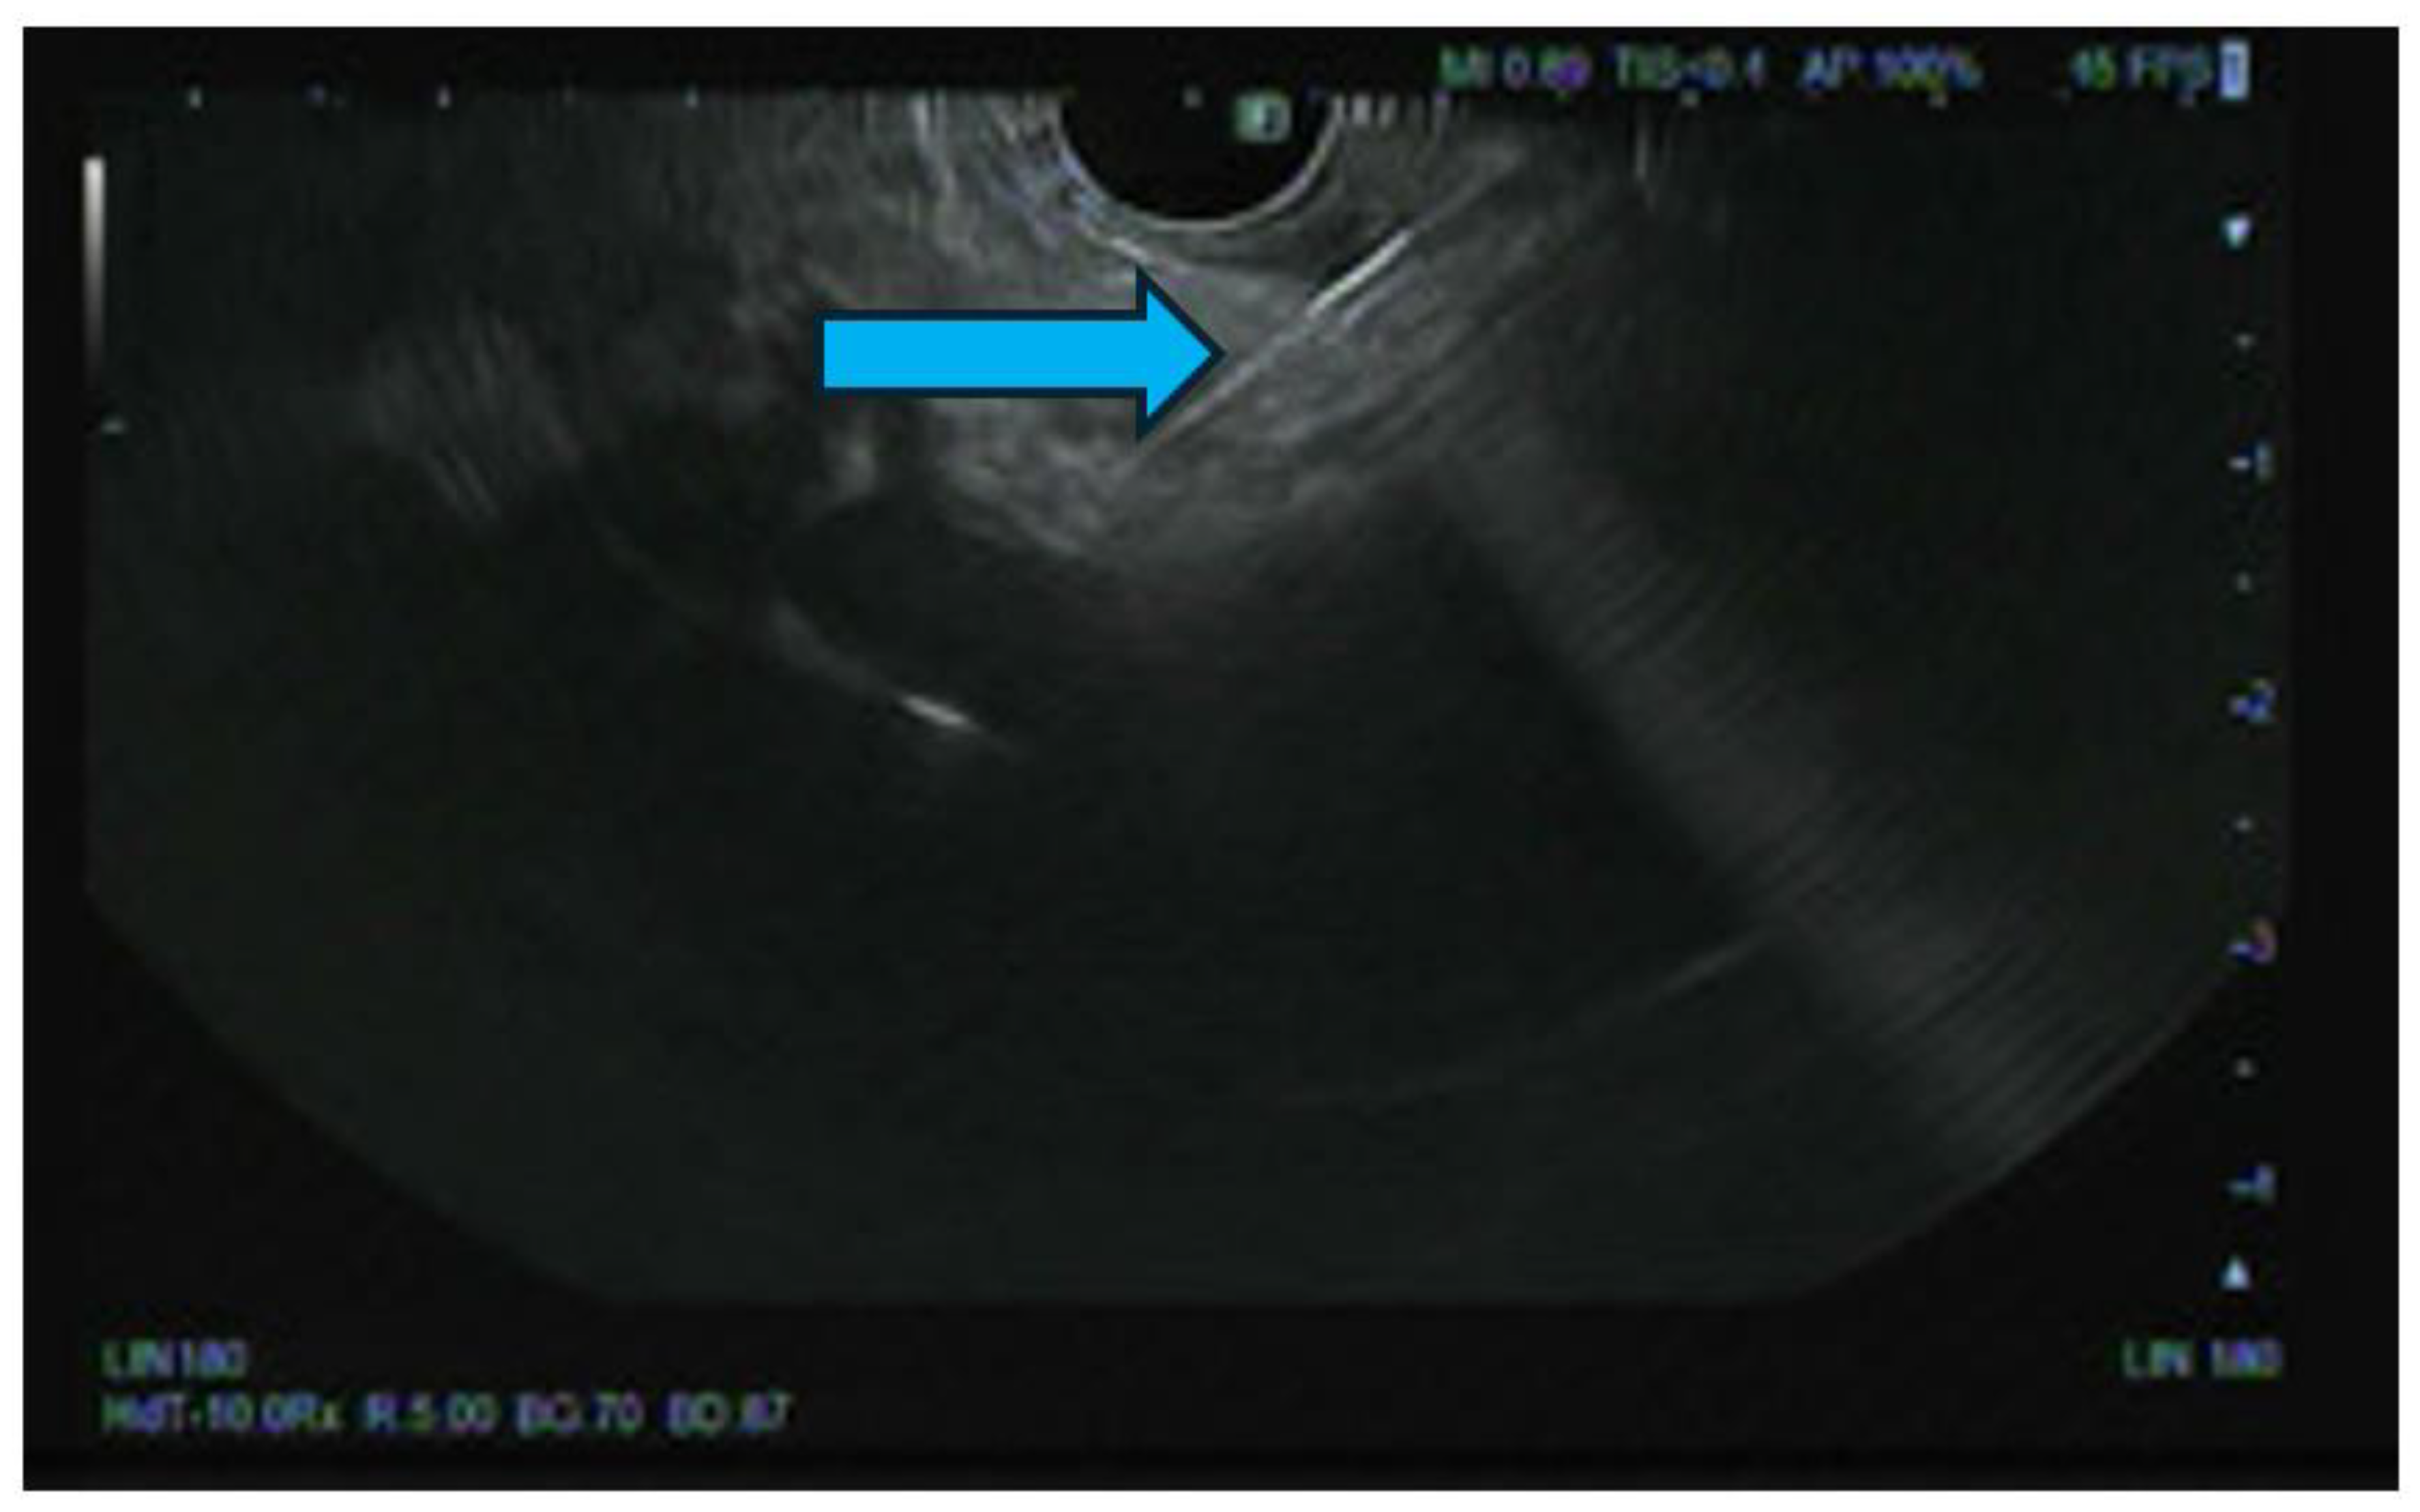

Pancreatic cancer is an aggressive malignancy, and the current 5-year survival rate in the United States, according to the Surveillance, Epidemiology, and End Results Program data, approximates 12%. Although the current standard for resectable pancreatic cancer most commonly includes neoadjuvant chemotherapy prior to a curative resection, surgery in the majority of patients has historically been palliative. The latter interventions include open or laparoscopic bypass of the bile duct or stomach in cases of obstructive jaundice or gastric outlet obstruction, respectively. Non-surgical interventional therapies started with percutaneous transhepatic biliary drainage (PTBD), both as a palliative maneuver in unresectable patients with obstructive jaundice and to improve liver functions in patients in whom surgery was delayed. Likewise, interventional radiologic techniques included placement of plastic and ultimately self-expandable metal stents (SEMS) through PTBD tracts in patients unresectable for cure as well as percutaneous cholecystostomy in patients who developed cholecystitis in the context of malignant obstructive jaundice. Endoscopic retrograde cholangiopancreatography (ERCP) and stent placement (plastic/SEMS) was subsequently used both preoperatively and palliatively, and this was followed by, or undertaken in conjunction with, endoscopic gastro-duodenal SEMS placement for gastric outlet obstruction. Although endoscopic ultrasound (EUS) was initially used to cytologically diagnose and stage pancreatic cancer, early palliation included celiac block or ablation for intractable pain. However, it took the development of lumen-apposing metal stents (LAMS) to facilitate a myriad of palliative procedures: Cholecystoduodenal, choledochoduodenal, gastrohepatic and gastroenteric anastomoses for cholecystitis, obstructive jaundice, and gastric outlet obstruction, respectively. In this review, we synopse these procedures which have variably supplanted surgery for the palliation of pancreatic cancer in this rapidly evolving field.